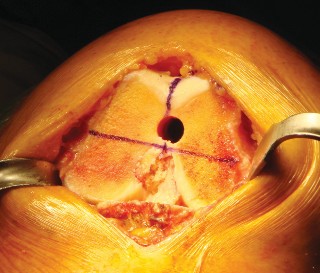

الخطوة 1: التحضير الأولي والوصول إلى المفصل

الوصول إلى المفصل (الشقوق):

يستخدم الأستاذ الدكتور محمد هطيف عادةً نهجًا جراحيًا طفيف التوغل (abbreviated trivector approach) للوصول إلى الركبة.

- يتم عمل شق جراحي يبدأ من الجزء الإنسي للحدبة الظنبوبية ويمتد إلى الجزء العلوي من الرضفة.

- يتم فصل ارتباط العضلة المتسعة الإنسية عن وتر العضلة الرباعية، مع الحرص على عدم تجاوز 3 سم فوق القطب العلوي للرضفة.

- يتم رفع غشاء الأنسجة الرخوة الإنسي بعناية وصولاً إلى الزاوية الخلفية الإنسية للركبة.

- يتم إزالة جزء من الوسادة الدهنية للرضفة.

- تُدفع الرضفة بعد ذلك إلى الميزاب الجانبي وتُثنى الركبة لزيادة كشف المفصل.

الخطوة 2: قطع عظم الفخذ (Femoral Cuts)

- الدليل داخل النخاع (Intramedullary Guide): يُستخدم دليل داخل النخاع لعظم الفخذ لضمان دقة القطع.

- ثقب كبير: يُحدث ثقب كبير في الجزء الأوسط من الشق بين اللقمتين.

- تحديد الزاوية: يُضبط الدليل داخل النخاع بزاوية 4 درجات ويُدخل في قناة الفخذ. يتم تركيب قالب القطع الفخذي البعيد (distal femoral cutting block) على الدليل.

- التثبيت والقطع: يُثبت القالب في مكانه ويُقطع الجزء البعيد من عظم الفخذ.